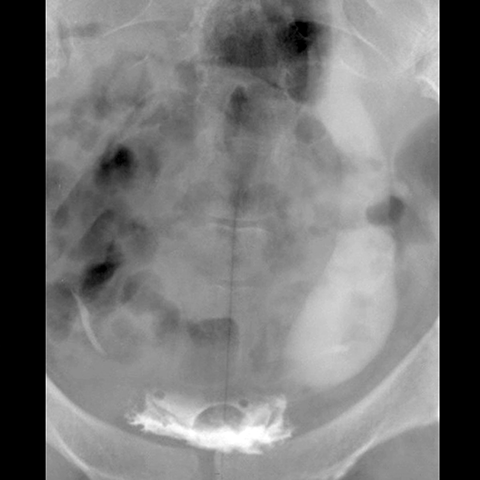

Ectopic duplicated ureter, plain film